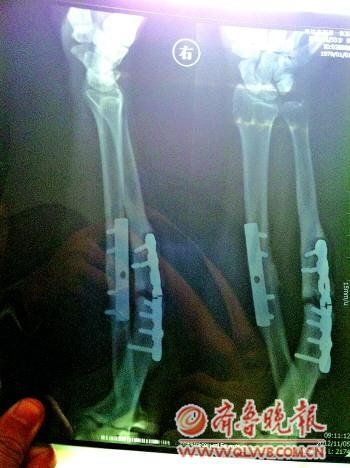

男子术后钢板断裂索赔15万元遭拒 院方愿做鉴定

(原标题:男子术后钢板断裂索赔15万元遭拒 院方愿做鉴定)